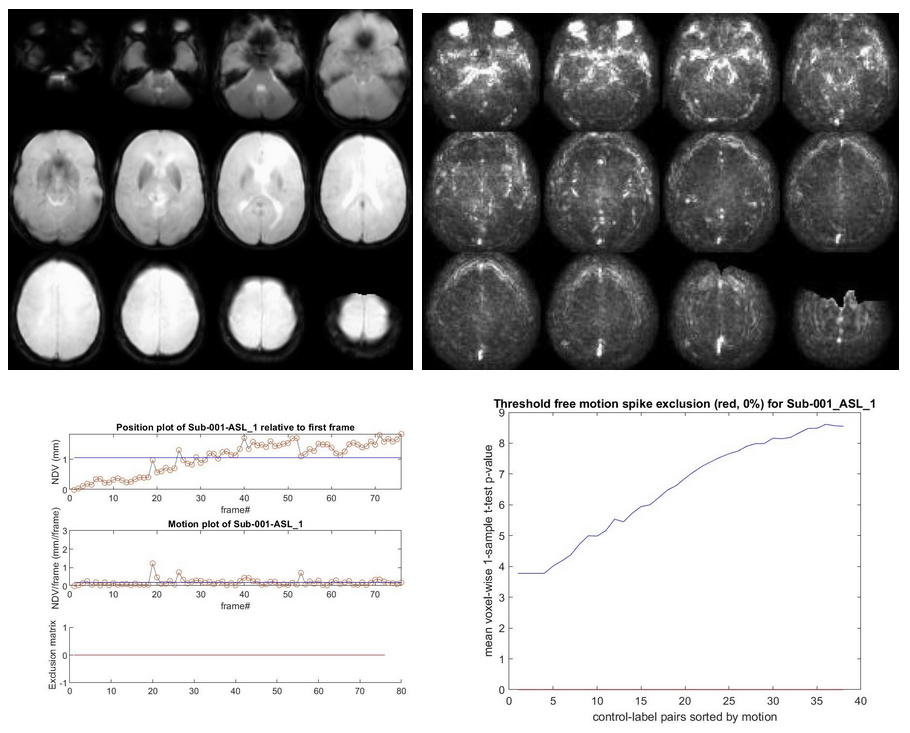

//Population/RawSourceIMCheck/Tra_mean_control_*.jpgfor the inspection of the average ASL source image//Population/SD_SNR/Tra_SD*ASL_*.jpgfor the temporal SD image. This should be a smooth, noisy image, with only vascular peaks.//Population/MotionASL/rp_*ASL*motion.jpgto inspect subject motion (net displacement vector)//Population/MotionASL/rp_*ASL*threshold_free_spike_detection.jpgto inspect the performance of ENABLE